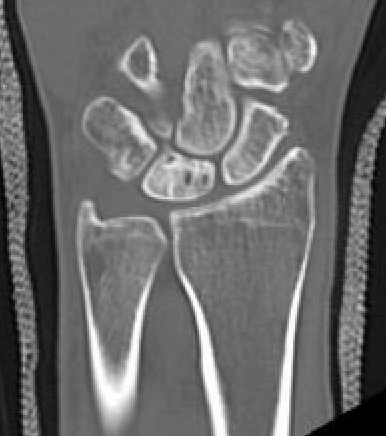

CT

Hesse et al J Hand Surg Eur 2025

- CT more accurate at gauging Kienbock's

- disease frequently worse on CT than assessed on xray

Lunate precollapse

CT demonstrating lunate fragmentation and collapse